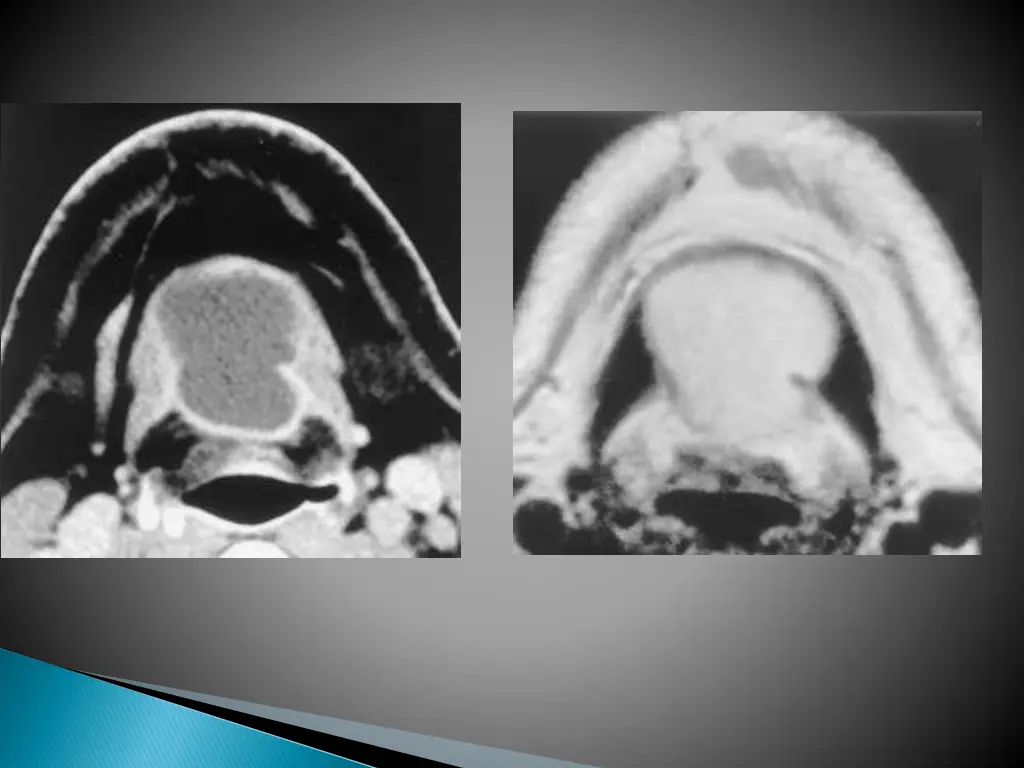

UNCOMPLICATED CYST : hypo on T1W and hyper on T2WI with smooth non enhancing wall. INFECTED/HAEMORRHAGIC CYST: thick irregular wall with enhancement. variable signal intensities depending on the protein content.

MRI better depicts the deep tissue extent. Cyst fluid hypo/hyper on T1W and hyperintense on T2WI. Occasionally, BEAK SIGN : on axial CT/MRI image : pathognomic of a 2ndbranchial cleft cyst especially bailey s type III cyst It represents a curved rim of tissue or a beak pointing medially between the ECA and ICA.